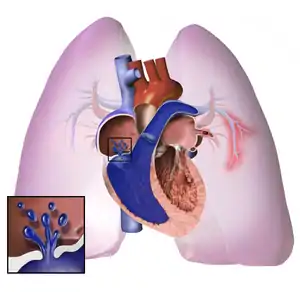

The pathogenesis of pulmonary arterial hypertension (WHO Group I) involves the narrowing of blood vessels connected to and within the lungs. This makes it harder for the heart to pump blood through the lungs, as it is much harder to make water flow through a narrow pipe as opposed to a wide one. Over time, the affected blood vessels become stiffer and thicker, in a process known as fibrosis. The mechanisms involved in this narrowing process include vasoconstriction, thrombosis, and vascular remodeling (excessive cellular proliferation, fibrosis, and reduced apoptosis/programmed cell death in the vessel walls, caused by inflammation, disordered metabolism and dysregulation of certain growth factors).[25][26] This further increases the blood pressure within the lungs and impairs their blood flow. In common with other types of pulmonary hypertension, these changes result in an increased workload for the right side of the heart.[12][27] The right ventricle is normally part of a low pressure system, with systolic ventricular pressures that are lower than those that the left ventricle normally encounters. As such, the right ventricle cannot cope as well with higher pressures, and although right ventricular adaptations (hypertrophy and increased contractility of the heart muscle) initially help to preserve stroke volume, ultimately these compensatory mechanisms are insufficient; the right ventricular muscle cannot get enough oxygen to meet its needs and right heart failure follows.[12][26][27] As the blood flowing through the lungs decreases, the left side of the heart receives less blood. This blood may also carry less oxygen than normal. Therefore, it becomes harder and harder for the left side of the heart to pump to supply sufficient oxygen to the rest of the body, especially during physical activity.[28][29][20] During the end-systolic volume phase of the cardiac cycle, the Gaussian curvature and the mean curvature of right ventricular endocardial wall of PH patients was found to be significantly different as compared to controls.[30]

In PVOD (WHO Group 1'), pulmonary blood vessel narrowing occurs preferentially (though not exclusively) in post-capillary venous blood vessels.[31] PVOD shares several characteristics with PAH, but there are also some important differences, for example differences in prognosis and response to medical therapy.

Persistent pulmonary hypertension of the newborn occurs when the circulatory system of a newborn baby fails to adapt to life outside the womb; it is characterized by high resistance to blood flow through the lungs, right-to-left cardiac shunting and severe hypoxemia.[12]

Pathogenesis in pulmonary hypertension due to left heart disease (WHO Group II) is completely different in that constriction or damage to the pulmonary blood vessels is not the issue. Instead, the left heart fails to pump blood efficiently, leading to pooling of blood in the lungs and back pressure within the pulmonary system. This causes pulmonary edema and pleural effusions.[32] In the absence of pulmonary blood vessel narrowing, the increased back pressure is described as 'isolated post-capillary pulmonary hypertension' (older terms include 'passive' or 'proportionate' pulmonary hypertension or 'pulmonary venous hypertension'). However, in some patients, the raised pressure in the pulmonary vessels triggers a superimposed component of vessel narrowing, which further increases the workload of the right side of the heart. This is referred to as 'post-capillary pulmonary hypertension with a pre-capillary component' or 'combined post-capillary and pre-capillary pulmonary hypertension' (older terms include 'reactive' or 'out-of-proportion' pulmonary hypertension).[11][14][33]

In pulmonary hypertension due to lung diseases and/or hypoxia (WHO Group 3), low levels of oxygen in the alveoli (due to respiratory disease or living at high altitude) cause constriction of the pulmonary arteries. This phenomenon is called hypoxic pulmonary vasoconstriction and it is initially a protective response designed to stop too much blood flowing to areas of the lung that are damaged and do not contain oxygen. When the alveolar hypoxia is widespread and prolonged, this hypoxia-mediated vasoconstriction occurs across a large portion of the pulmonary vascular bed and leads to an increase in pulmonary arterial pressure, with thickening of the pulmonary vessel walls contributing to the development of sustained pulmonary hypertension.[20][34][35][36] Prolonged hypoxia also induces the transcription factor HIF1A, which directly activates downstream growth factor signaling that causes irreversible proliferation and remodeling of pulmonary arterial endothelial cells, leading to chronic pulmonary arterial hypertension.

In CTEPH (WHO Group 4), the initiating event is thought to be blockage or narrowing of the pulmonary blood vessels with unresolved blood clots; these clots can lead to increased pressure and shear stress in the rest of the pulmonary circulation, precipitating structural changes in the vessel walls (remodeling) similar to those observed in other types of severe pulmonary hypertension. This combination of vessel occlusion and vascular remodeling once again increases the resistance to blood flow and so the pressure within the system rises.[37][38]